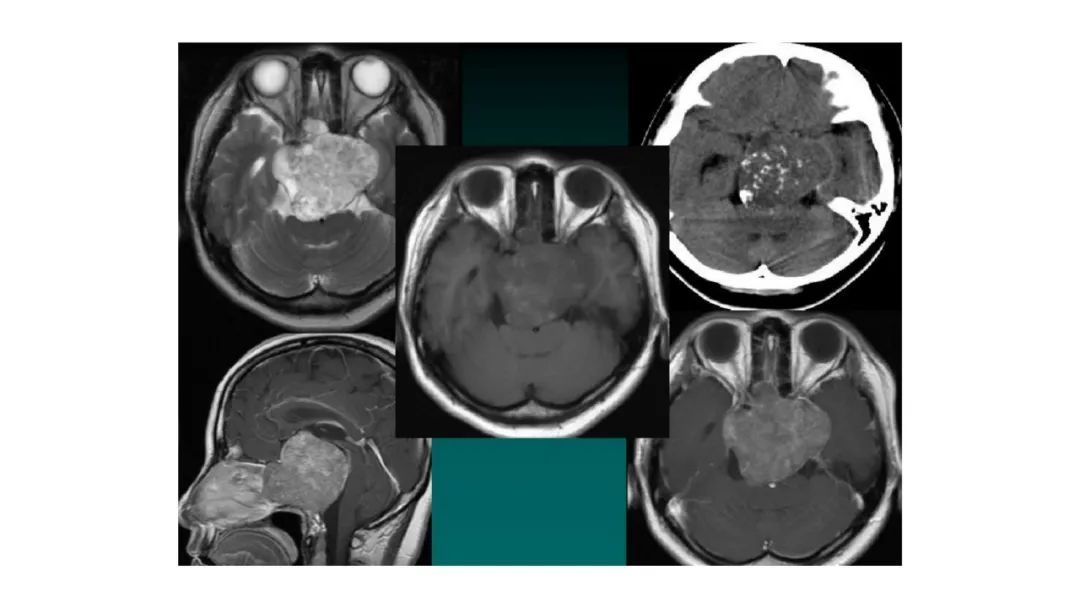

颅脑影像诊断基础知识讲座:颅骨病变